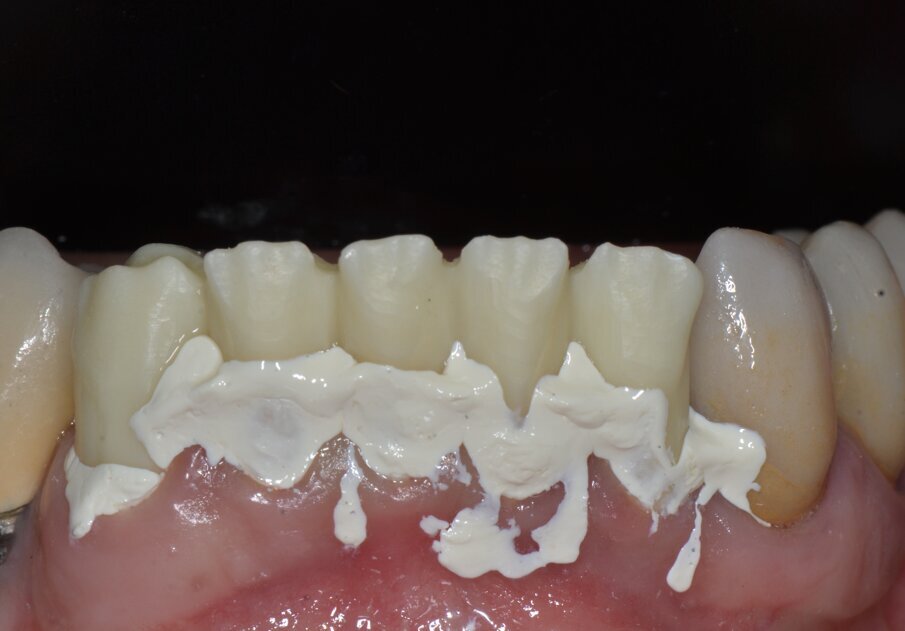

Le impronte per il restauro definitivo vengono rilevate tramite polieteri con tecnica in un tempo a due fasi e cucchiai individuali e tecnica di retrazione gengivale con doppio filo.